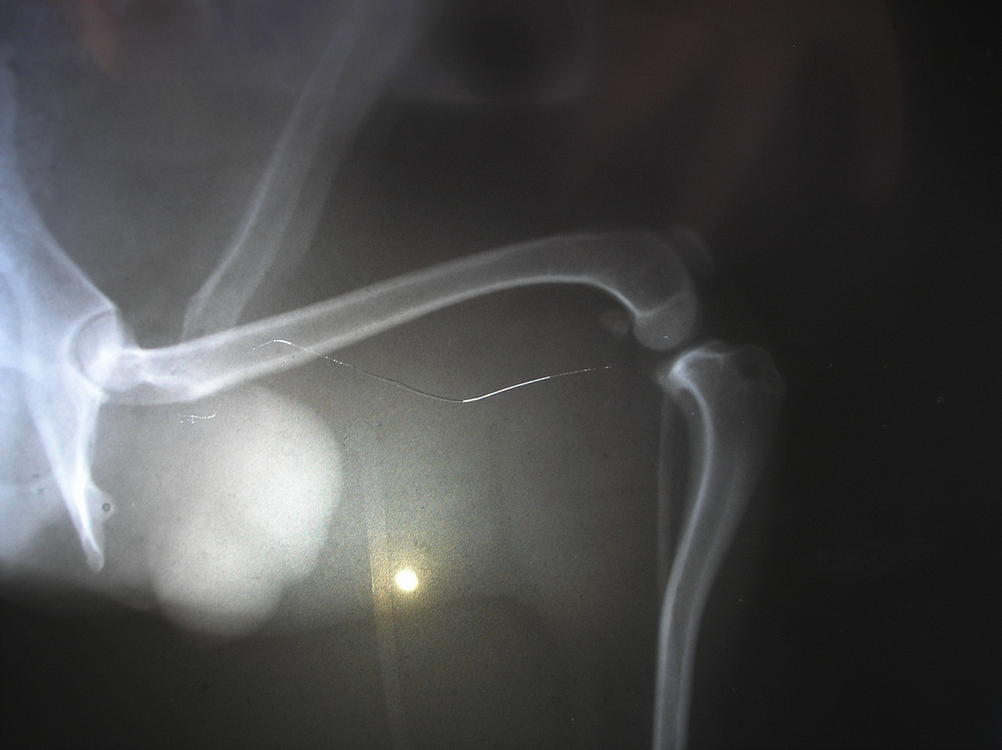

Мы сегодня сделали рентген с анестезией, на правом 2ая степень, на левом нестабильность, т.е. 1ая степень...травматолог говорит нужна операция, день правда еще не назначили...:flushed:

Вот наши результаты:

Я не отказалась, т.к. по этому рентгену даже я увидела все это!(

Плюс его нормально осмотрели (пока под наркозом был), правая коленка совсем болтается и левая тоже нестабильная. Завтра закажут все материалы специально для Тоськи и назначат день. На левой травматолог хочет укрепить связку, чтобы вывиха не было, а правую оперировать по полной! Надеюсь, нам это поможет жить полноценной жизнью, а пока покой-покой-покой!